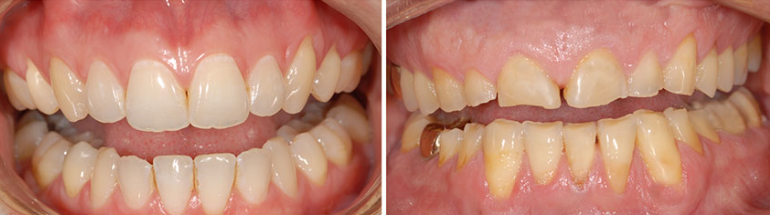

Case Study 1: Combined Erosion and Attrition

Patient Profile: 45-year-old male with complaints of increasing sensitivity and esthetic concerns related to shortened anterior teeth.

Clinical Findings:

- Generalized thinning of enamel on palatal surfaces of maxillary anterior teeth

- Cupped-out lesions on first molars

- Flattened incisal edges with matching wear facets

- History of GERD and occasional clenching reported during stress periods

Diagnostic Assessment: Combined erosion from GERD and attrition from stress-related clenching.

Treatment Approach:

- Medical referral for GERD management

- Dietary counseling to reduce acidic beverage consumption

- Custom occlusal night guard fabrication

- Direct composite restorations for posterior cupped-out lesions

- Feldspathic veneers for anterior teeth to restore esthetics and protect remaining tooth structure

Outcome: Six-month follow-up revealed stabilization of wear pattern, resolution of sensitivity, and high patient satisfaction with esthetic results.